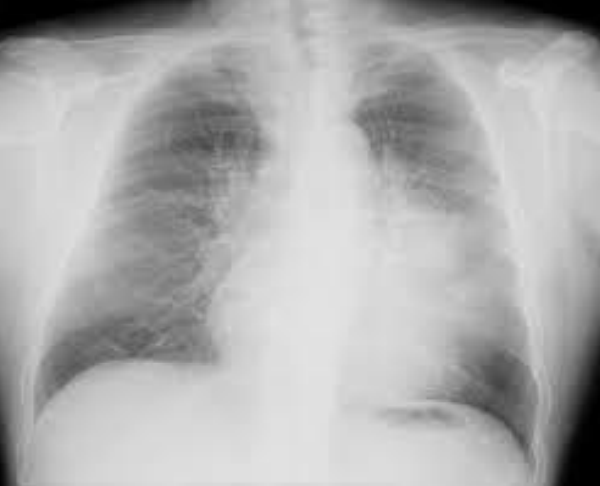

Esta es una radiografía de:

Mediastino